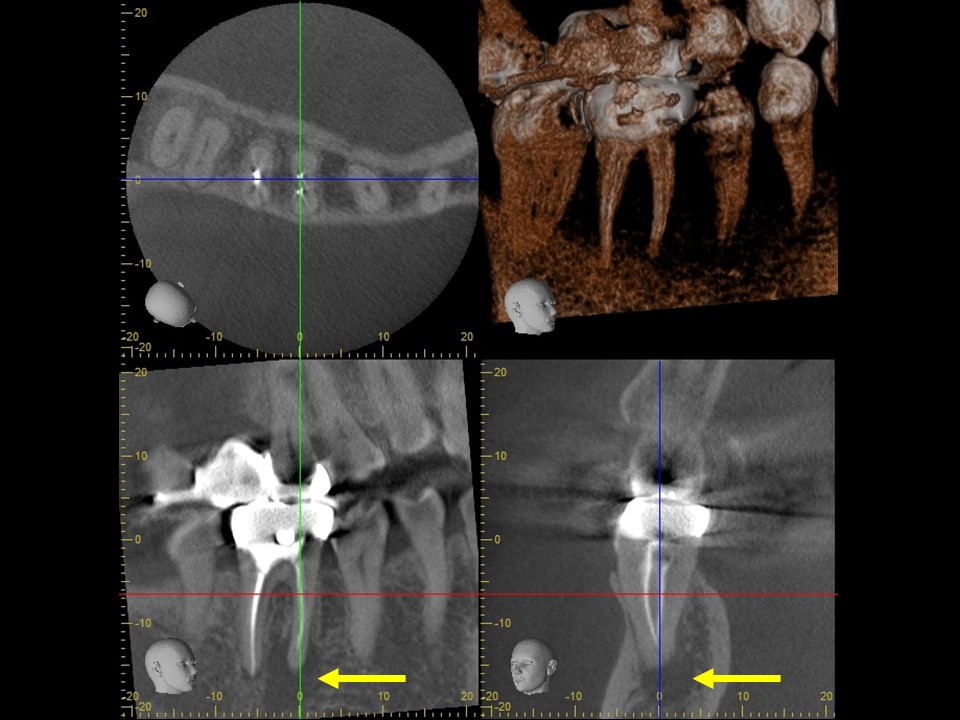

初診時レントゲンおよびCT画像です。すでに根管治療はされているが、根尖まで薬が入っておらず、根尖病変と思われる黒い透過像を認めます(矢印)

症状が消失したため、ガッタパーチャとバイオセラミックシーラーにて根管充填を行いました。炎症が強かったため、歯槽骨の吸収の範囲が術前よりも広がっています(矢印)。